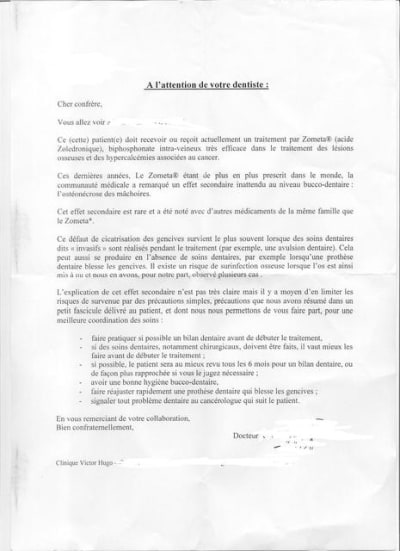

Les recommandations actuelles pour extraire sous biphosphonates , en cas de nécessité absolue, sont :

- l'atraumatisme (alvéolectomie et lambeaux déconseillés+++,),

-la converture ATB doit être de 3 semaines (pas 7 jours) avc association amoxicilline et métronidazole, voire plus longtemps tant que la cicatrisation parfaite n'est pas obtenue

- sutures passives sans tensions tissulaires

- bain-de- bouche 72 heures après l'acte, pas avant.

Arrêt biphosphonates inutiles car rémanents longtemps (mois/années)

Si l'on peut éviter, ne pas faire l'extraction (ici çà ne semble ps être possible!!): obturer, arraser la dent non restaurable jusqu'à ce qu'elle soit sous-gingivale et laisser tel quel. C'est ce qui est recommandé.

En tout cas, surveiller+++ et prévenir le patient des risques : faut obtenir son accord.Il est aussi recommandé de prendre contact avec les préscripteurs...

... c'est très bien que les prescripteurs prennent conscience de ce problème.